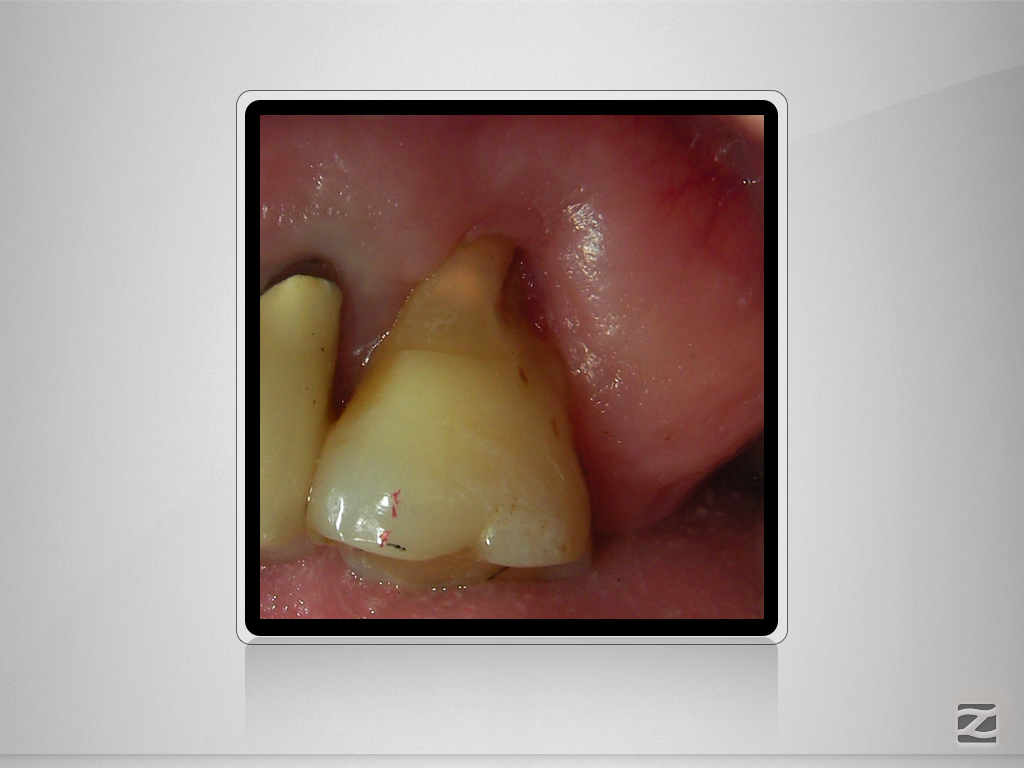

27D.009

Vorher/Nachher – Die Auflösung